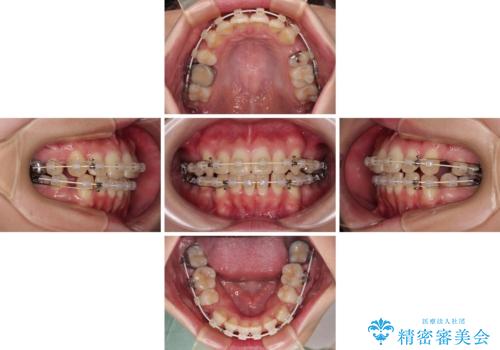

- 矯正装置

- 審美装置

- 八重歯やクロスバイトを気にして来院された患者様です。

口元の突出感はありませんでしたが、デコボコが強く、非抜歯矯正とすると出っ歯仕上がりとなる可能性があったため、上下左右の第一小臼歯4本を抜歯し、ワイヤー装置にて矯正治療を行うこととしました。